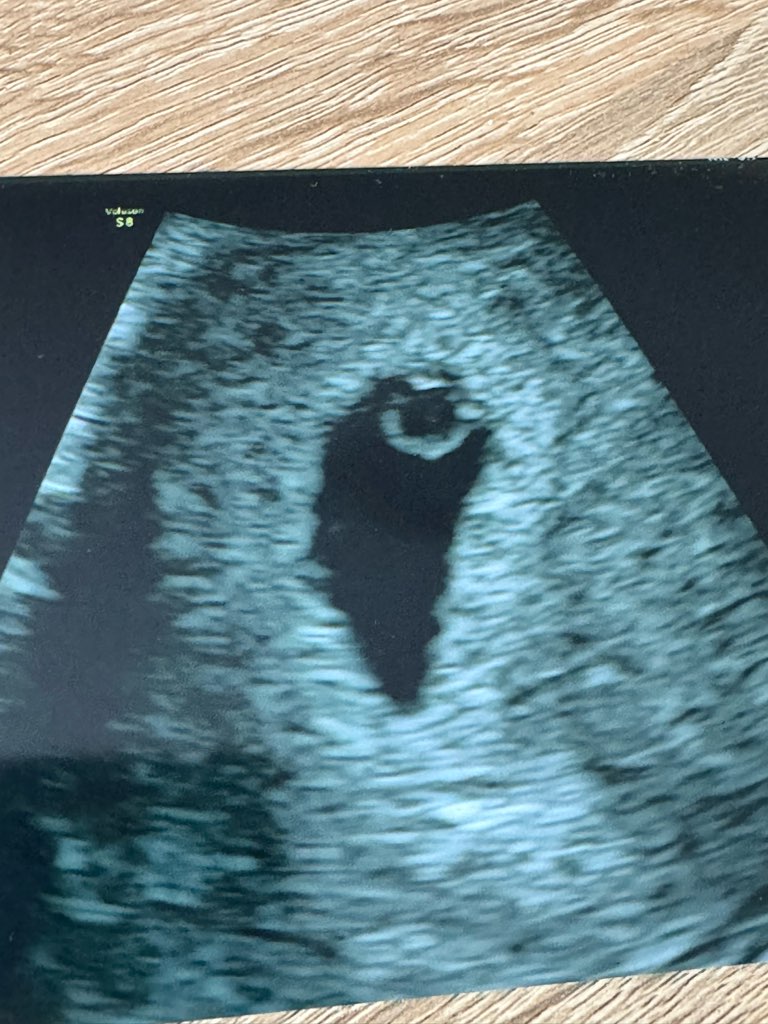

Właśnie wróciłam z pierwszego USG. Ogólnie wg miesiączki powinien być dzisiaj 6+0 tydzień ciąży (lecz średni cykl to 32 dni) ale według USG jest to 4+5. Trochę rozbieżność mnie martwi ponieważ wiem kiedy miałam owulację . Ale najważniejsze że tam u góry nad ciałkiem żółtym jest maluteńki zarodek 1,4mm z widocznym, bijącym serduszkiem . Troszkę pocieszam się tym , że sprzęt raczej nie był najlepszy i chwilkę się Pani naszukała fasolki , ale w końcu dojrzałyśmy .